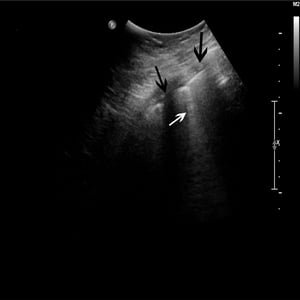

超声心动图可以帮助区别引起肺水肿的病因(如, 心梗 、瓣膜功能不全、高血压性心脏病及 扩张型心肌病 ),并影响治疗选择。